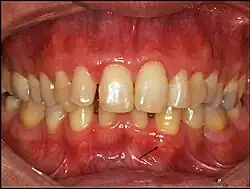

O cisto gengival do adulto tende a se apresentar como uma lesão nodular firme bem delimitada, com coloração normal, transparente ou tendendo ao azul-arroxeado, na mucosa gengival de adultos.[2] O cisto gengival do neonato é uma lesão nodular bem delimitada e esbranquiçada na mucosa alveolar de um recém-nascido.[3] Anteriormente, o CGN foi chamado de pérola de Epstein, ou nódulo de Bohn, mas essas nomenclaturas não são utilizadas atualmente por serem diferentes do CGN:[3]

O cisto gengival tende a não ser visível em radiografias por sua origem ser exclusivamente de tecidos moles, mas em raros casos, seu crescimento pode gerar uma sombra radiolúcida ao causar a erosão óssea, e em alguns casos pode até mesmo se assemelhar ao cisto periodontal lateral pelo aspecto radiolúcido bem delimitado.[2]